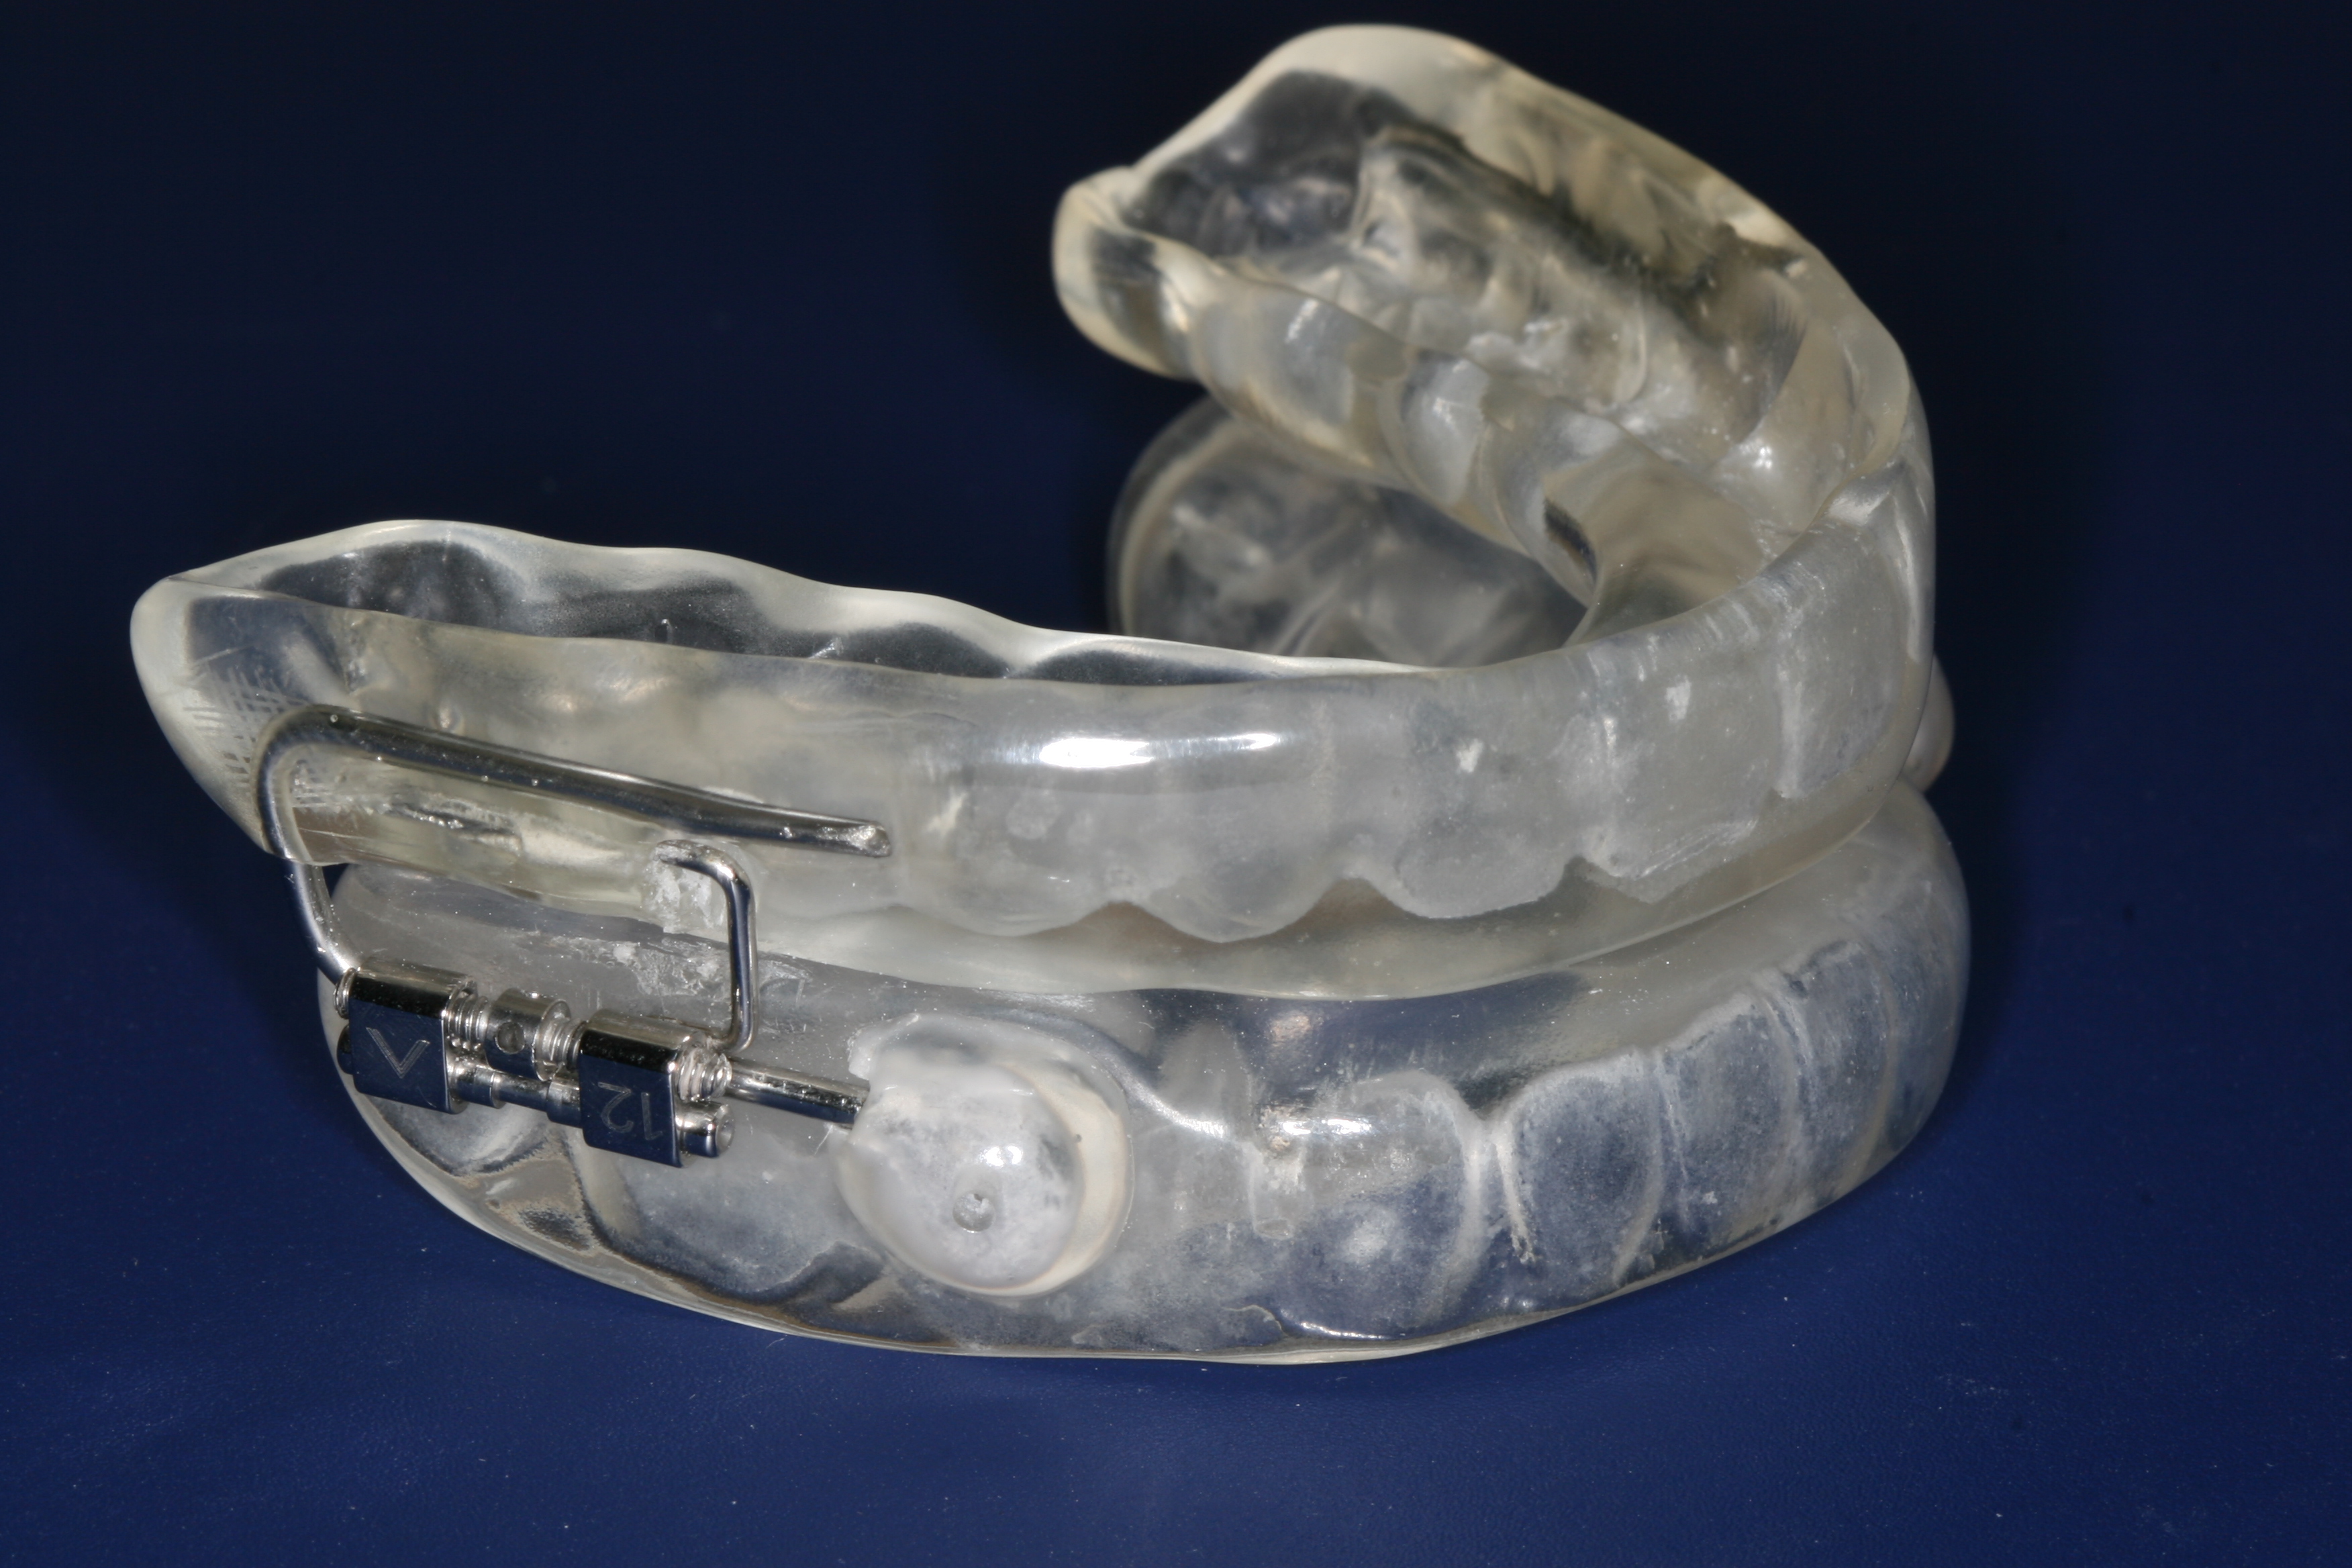

- Sleep Apnea Devices - Custom-fitted oral appliances to help manage sleep apnea symptoms.

Dental x-rays also serve as a critical tool in planning complex dental treatments such as orthodontics, implants, and extractions. The detailed imagery helps create precise treatment plans tailored to each patient's unique anatomy. To explore how modern technology is shaping these plans, visit our page on digital dentistry benefits.